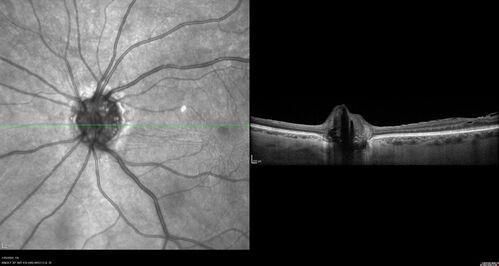

Optic Disc Drusen - Calcified

Disc Drusen Calcified